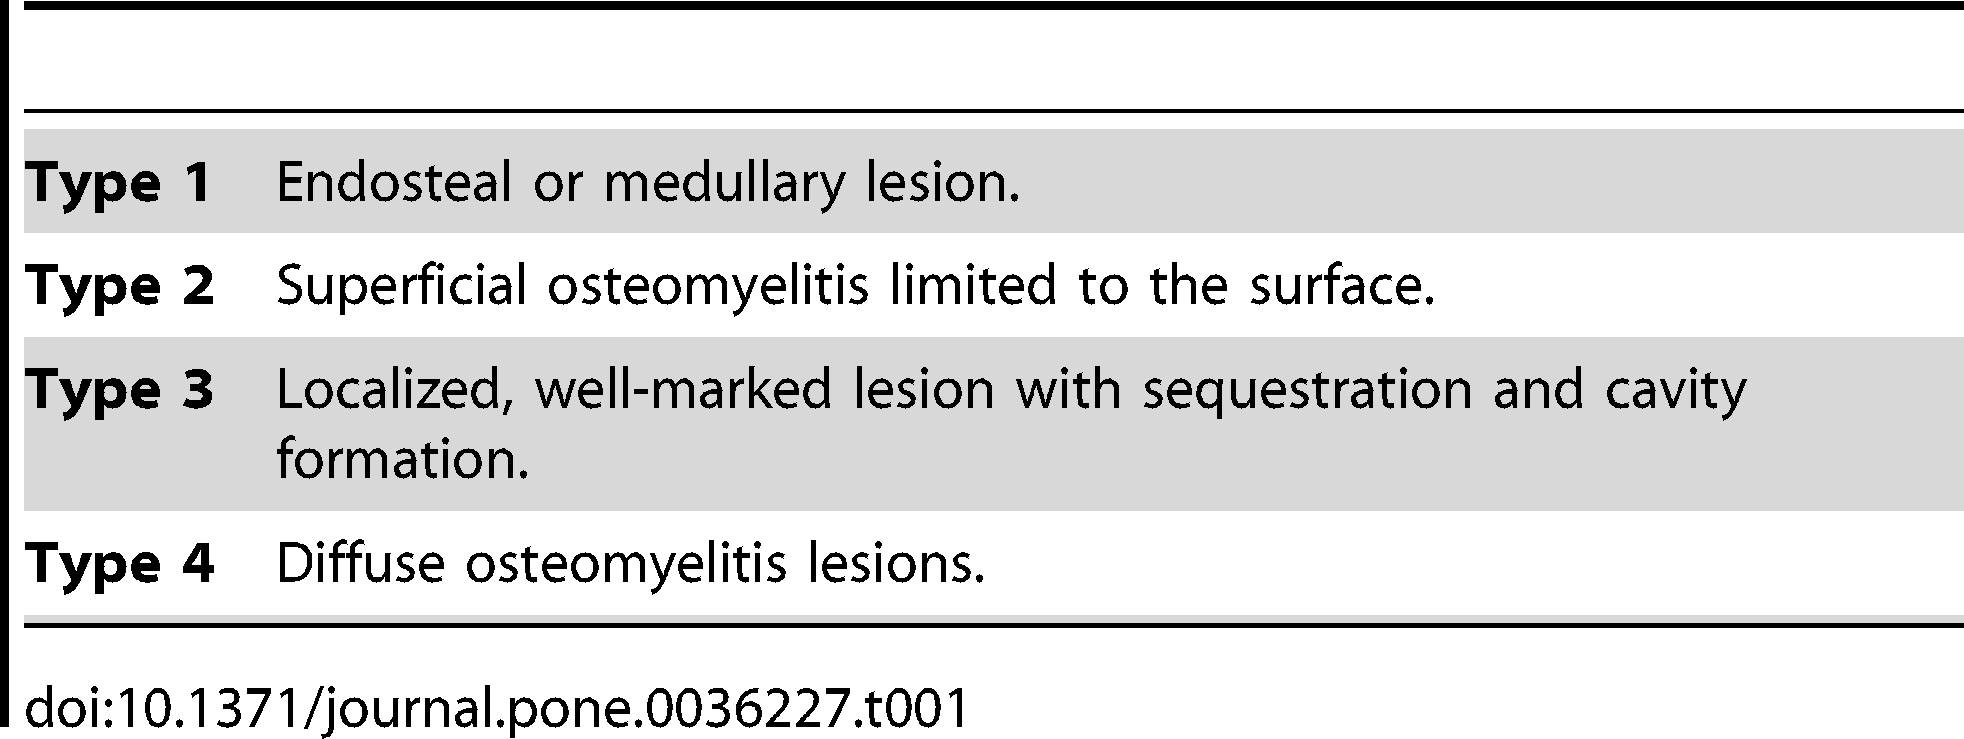

Distributions of Cranial Pathologies Provide Evidence for Head-Butting in Dome-Headed Dinosaurs (Pachycephalosauridae)

Peterson, J.E., Dischler, C. & Longrich, N.R. · PLOS ONE

Estudo definitivo sobre o comportamento de choque de cabeças em pachicefalossaurídeos, baseado na análise sistemática de 109 cúpulas cranianas de espécimes adultos. Peterson, Dischler e Longrich encontram que 22% dos espécimes adultos com cúpula desenvolvida apresentam lesões patológicas concentradas no ápice da cúpula, compatíveis com osteomielite crônica resultante de traumatismo repetido e infecção secundária. Formas de cabeça plana, interpretadas como juvenis ou fêmeas, não apresentam patologias. O padrão de distribuição das lesões, a composição de osso fibrolamelado com fibroblastos capazes de remodelação rápida e a comparação com bovídeos modernos que se combatem sustentam o comportamento de choque de cabeças e/ou flancos como habitual nos pachicefalossaurídeos adultos de cúpula desenvolvida.